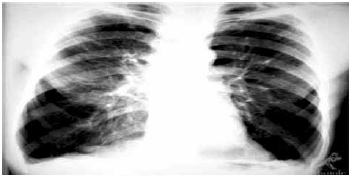

O rX é mais compatível com quadro de